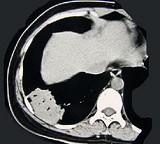

问题 女,39岁,咳嗽伴轻微胸痛,CT检查如图,最可能的诊断是 ( )

选项 A.右下肺节段性不张 B.右下肺脓肿 C.右下肺周围型肺癌 D.右下肺炎性假瘤 E.右下肺肺泡细胞癌

答案 D